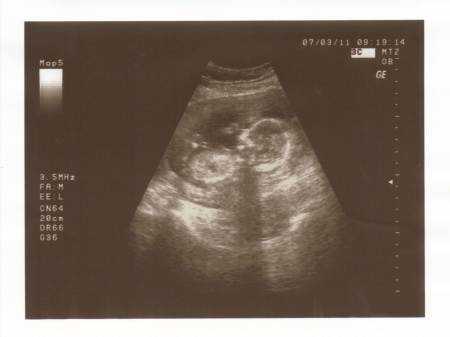

4. Jak vypadá miminko 16. týden těhotenství?

Plod v 16. týdnu těhotenství (šipkami označena levá ruka s prstíky, paže, páteř).